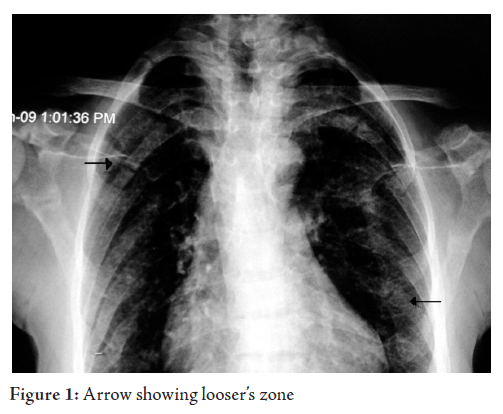

were within normal limits. Chest X ray showed normal parenchyma with looser’s

zones. (Fig. 1, 2)

The “pseudo-fractures” typically show as transverse zones of rarefaction, varying in

width from 1 mm to 1 cm. They are multiple and generally symmetrical in

distribution, and often occur in apparently normal bone. Their distribution is

mainly ischio-pubis, ilio-pubis, femur, tibia, radius, fibula, or at the iliac

bone. 4 Other common sites are the lower

ribs and the infraglenoid region of the scapula.